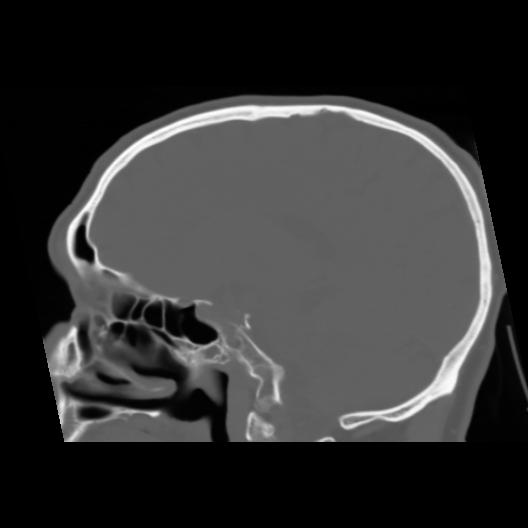

6 CEREBRO,,Sagittal,3.000,CEREBRO,Sagittal,